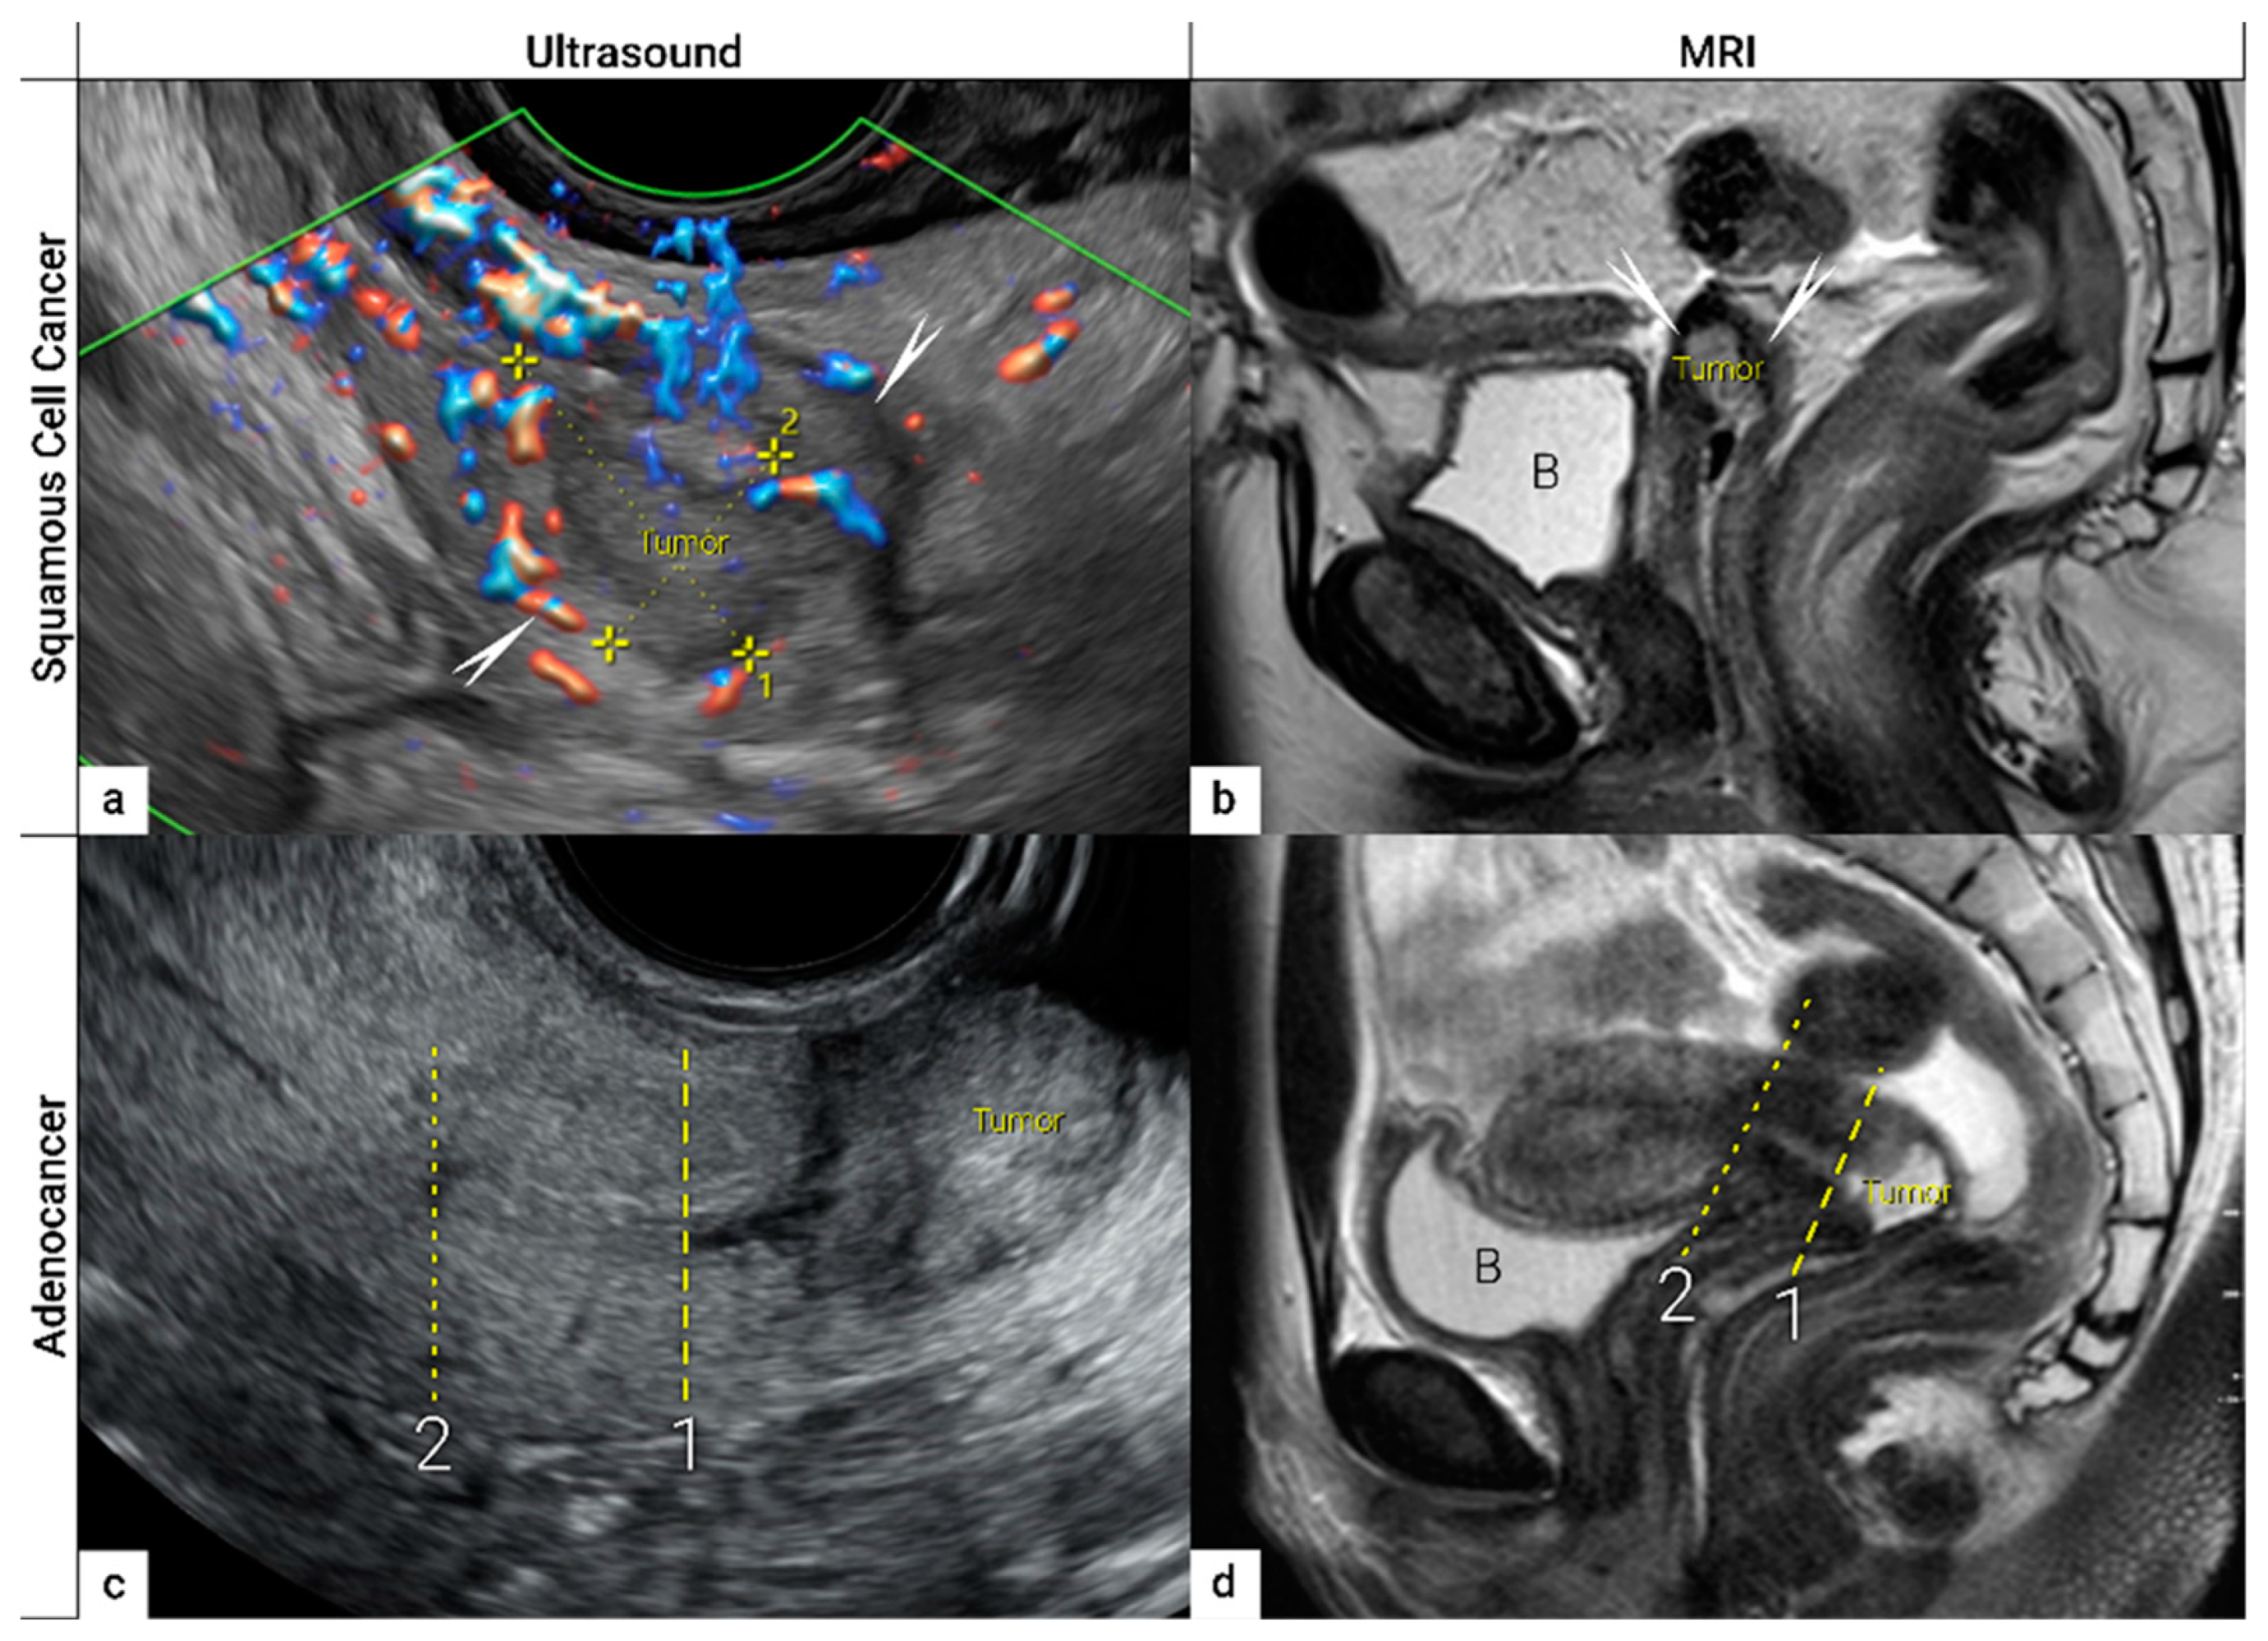

| IB | Carcinoma with deepest stromal invasion>5 mm, limited to the cervix uteri with size measured by maximum tumour diameter. | US: Highly vascularized hypoechogenic (squamous-cell carcinoma) or iso- / hyperechogenic lesion (adenocarcinoma) with intact hyperechogenic pericervical fascia and positive sliding sign between tumour and bladder/rectum. MRI: Tumour has intermediate to high signal on T2W images. Dynamic CE-T1W images depicts tumour as hyperintense in the arterial phase and iso- or hypointense in the venous phase. Tumours characteristically exhibit restricted diffusion on DWI (hyperintensity on high b-value images and low intensity on the ADC maps). Tumor does not disrupt the hypointense peripheral stromal ring (best seen on T2W images). |

| T2a | IIA | Involvement limited to the upper two-thirds of the vagina without parametrial invasion | US: Highly vascularized tumour infiltrates upper two third of hypoechogenic vaginal wall, maximum diameter of primary tumor is critical to substageT2a1/T2a2. MRI: Involvement of the upper two-third of the vagina is seen as segmental loss of the T2-hypointensity of the vaginal wall. |

- Epstein, E.; Di Legge, A.; Masback, A.; Lindqvist, P.G.; Kannisto, P.; Testa, A.C. Sonographic characteristics of squamous cell cancer and adenocarcinoma of the uterine cervix. Ultrasound in obstetrics & gynecology : the official journal of the International Society of Ultrasound in Obstetrics and Gynecology 2010, 36, 512–516. [Google Scholar] [CrossRef]